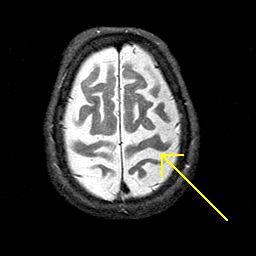

Alzheimer's disease MR T2-weighted -- Slice #40

Tour 1: Next/Previous/Start: This tour will examine the brain of an elderly woman with Alzheimer's disease. This brain displays many of the commonest features of the disease: brain shrinkage, or atrophy, and loss of function, as indicated by hypoperfusion (described in Tour 2). First, look at the prominent sulci, especially the central sulcus. Some reduction in brain volume is a part of normal aging, but compare this brain with the normal central sulcus, from a normal 81 year old woman. The abnormal shrinkage seen in this case, while not a finding specific to Alzheimer's disease, is severe and seems to affect some regions more than others.